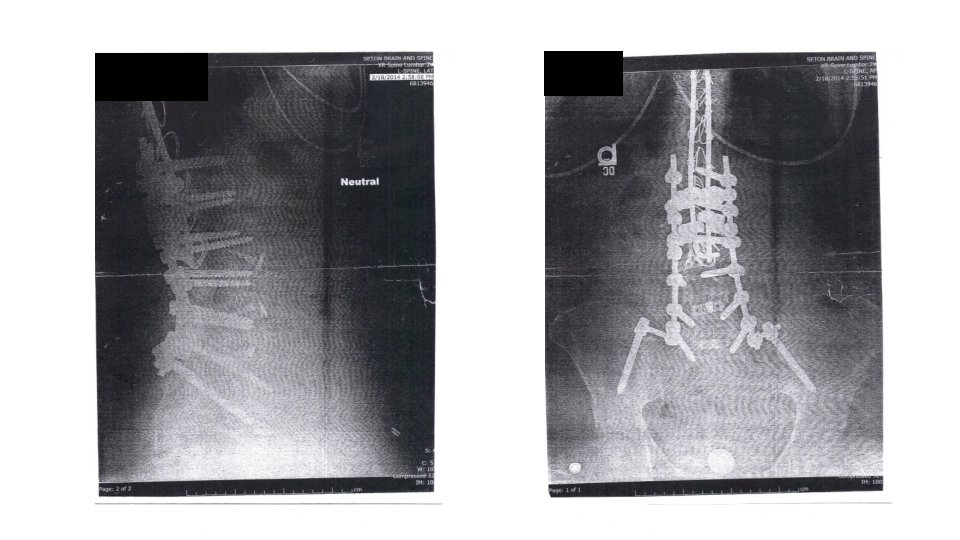

Surgical Hx • 1982: T 8 to S 1 fusion to correct scoliosis • February 2014: T 8 to S 1 fusion to correct long standing complications from 1982 surgery • December 2013, presented in ER with complaints of severe pain • Internal hemorrhaging, spontaneous cerebrospinal fluid leak, and atrial fibrillation • Resulted in 10 hospitalization • During corrective surgery, the pudendal and hypogastric afferent nerves around the bladder were damaged, resulting in DSD